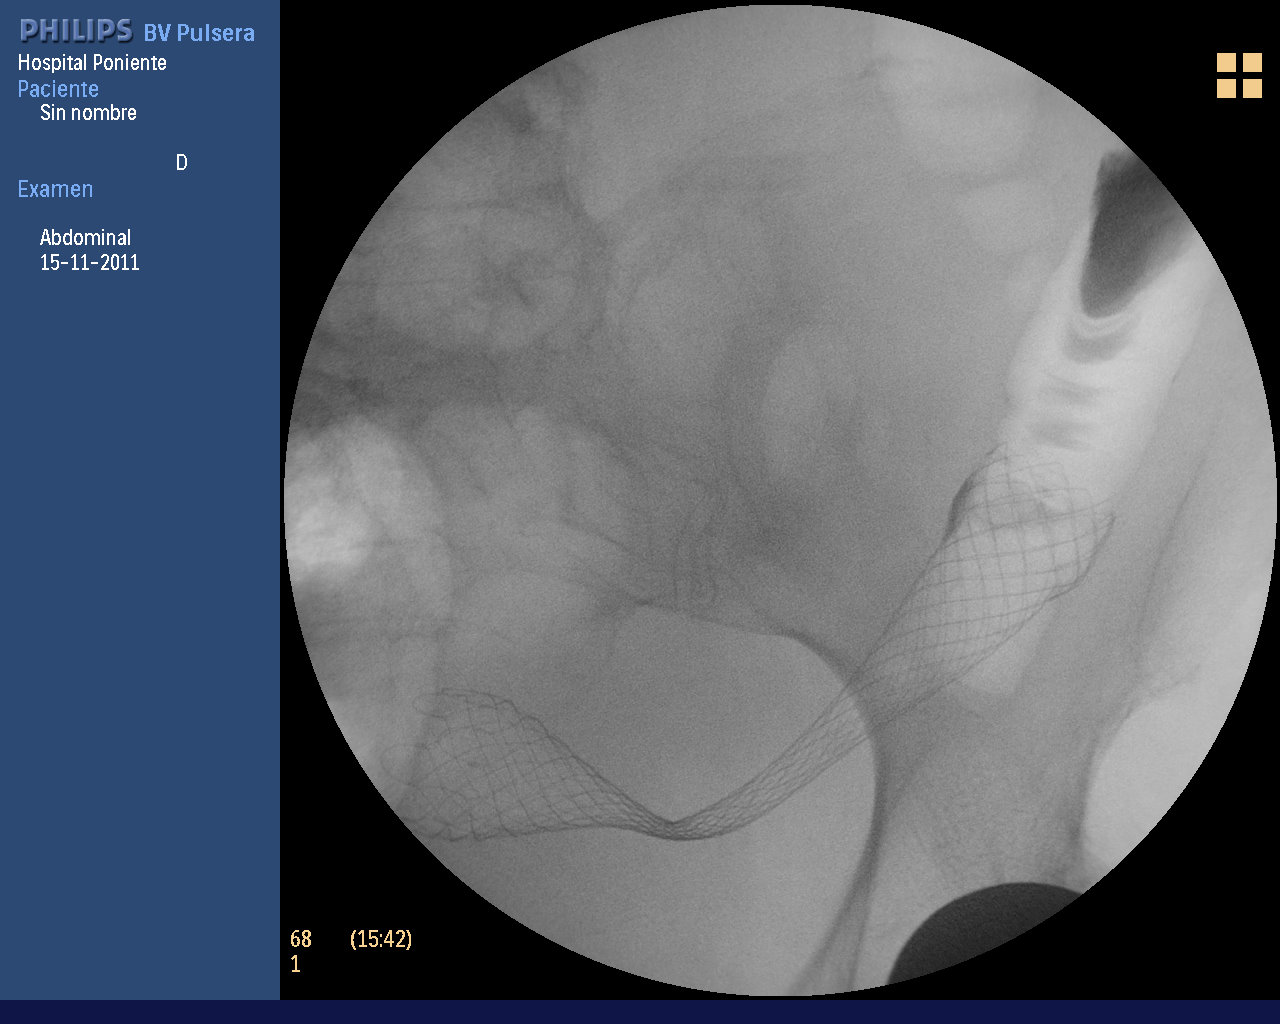

Paciente mujer, de 65 años de edad con antecedentes de demencia tipo Alzheimer avanzada, DM tipo II en tratamiento con Insulina y prótesis de cadera. Ingresa por un cuadro constitucional de dos meses de evolución junto a anemia ferropénica severa y dolor abdominal de tipo cólico acentuado en las últimas 48 horas, sin emisión de gases ni heces con distensión abdominal importante. Se realiza un TAC abdominal con contraste iv, donde se aprecia un engrosamiento circunferencial nodular del sigma proximal, en un segmento de aproximadamente 8,5 cl de longitud, compatible con neoformación. Desflecamiento del contorno seroso y aumento de la densidad del tejido graso mesosigmoideo compatible con infiltración. La lesión contacta con el peritoneo parietal pélvico izquierdo adyacente, apreciándose una leve retracción del mismo y realce aumentado con respecto al contralateral, sugestivos de invasión peritoneal parietal. Se decide colocar un stent de colon no recubierto conla doble intención terapéutica: paliación y desobstrucción del colon con éxito.

Bajo mi punto de vista, lo interesante de este caso es que presenta la mayor parte de las dificultades que un endoscopista se puede encontrar en la colocación de una protesis de colon por una oclusión neoplásica. En primer lugar, la friabilidad del tejido neoplásico hace dificil el paso de la guía a través de la estenosis, que además está situado en pleno sigma. Por otro lado, la longitud de la estenosis (cercana a los 9 cms), obliga el reajuste lo mas estricto posible de la prótesis (la mayor longitud de las nuestras es de 12 cms, teniendo en cuenta que hay que intentar dejar entre 1.5 y 2 cm por encima y por debajo de los extremos de la estenosis). Por ese motivo, teniendo en cuenta el bucle típico en alfa que se forma en la unión RS y la longitud de la estenosis, suele ser difiil tanto el paso del dispositivo liberador como la liberación y su ajuste con control conjunto endoscópico-fluoroscópico. Para el paso del sistema liberador, hay que ir traccionado de la guía (cuanto mas gruesa y rígida sea, mejor. Se aconsejan de 0.035-0.038″), sin que se formen acodaduras de ésta última. Posteriormente hay que ir liberando muy lentamente la prótesis, controlando conjuntamente la visión fluoroscópica (extremo distal al operador sobre todo) con la endoscópica (extremo proximal al operador). El control de las 3 marcas radiopacas de la prótesis (marca distal, marca medial que refleja el punto de no retorno en el reenenvainado y marca proximal) es también muy importante. Finalmente se consigue centrar de forma muy adecuada la prótesis.